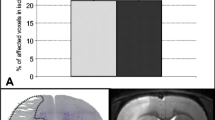

We used a single i.c.v. injection of 1 × 1010 AAV-VEGF-C particles per mouse as it has been shown to induce significant lymphangiogenesis in dorsal and basal dLVs as reported previously [8]. We verified VEGF-C expression in different brain areas after similar VEGF-C injection (Fig. 1a, b). Quantitative real-time PCR (qPCR) revealed a significant increase of Vegfc transcripts in RNA isolated from various brain regions two weeks after the AAV-VEGF-C injection vs AAV-Ctrl (without payload). The increase in VEGF-C vs. Ctrl mice was ≥ twofold in the cerebellum and olfactory bulb (p < 0.001), and ~ 1.5-fold in the cortex (p < 0.01) (Fig. 1c). In contrast, the expression of Aquaporin4 (Aqp4) mRNA, which encodes a water channel protein expressed in astrocyte endfeet at the interface between brain and blood circulation [35], was not altered in VEGF-C vs. Ctrl mice (Fig. 1d). These data suggest that i.c.v delivery of VEGF-C induces increased Vegfc expression in the brain without affecting Aqp4 expression.

AAV-VEGF-C transduction increase in Vegfc mRNA in several brain regions. a Experimental outline showing time points for administration and sample taking. b A schematic illustration of the AAV injection site 14 days before sample taking. c Vegfc and d Aqp4 gene expression levels in cortex, cerebellum (ipsi- and contralateral to inj.), hippocampus, olfactory bulb, and striatum 2 weeks after Ctrl and VEGF- C injection. n = 5–6/per group; data points represent individual mice. P values were calculated with ordinary one-way ANOVA with Tukey’s post hoc multiple comparison test. Data are expressed as mean ± SEM, ***p < 0.001. CB cerebellum, Ctx cortex; HC hippocampus; OB olfactory bulb; Str striatum

Overexpression of VEGF-C Does Not Affect Ischemia-Induced Brain Infarct Volume or Edema

To study how VEGF-C affects the development of stroke, we injected adult mice with AAV-VEGF-C or AAV-Ctrl 14 or 35 days before tMCAo surgery (Fig. 2a, b). MRI-based quantification at 3 dpi did not reveal significant differences in the brain infarct or edema volumes between VEGF-C and Ctrl mice subjected to either treatment schedule (Fig. 2c–e). These findings indicated that i.c.v delivery of VEGF-C prior to stroke did not affect infarct expansion.

Infarct and edema volumes are not altered by VEGF-C overexpression. a, b Experimental outlines showing time points for administration, ischemic surgery, behavioral testing, and sample taking. c, d Infarct and edema volumes (%) of mice injected i.c.v. with Ctrl or VEGF-C at c 14 and d 35 days prior to ischemic surgery. e, f Exemplary T2-weighted MRI-series at 3 dpi of ischemic mice treated with either (e) VEGF-C or (f) Ctrl at − 14 dpi. n = 8–11; data points shown in graphs c and d represent individual mice. P values were calculated using two-tailed Student’s t test, p > 0.05